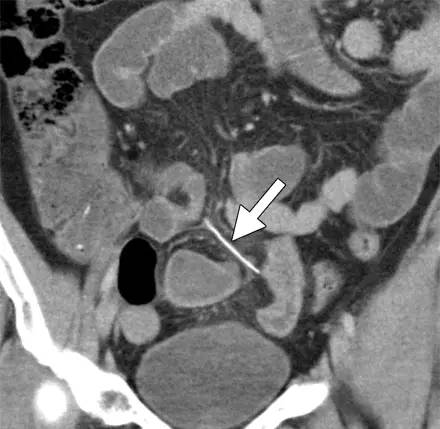

刺穿肠壁的鱼刺